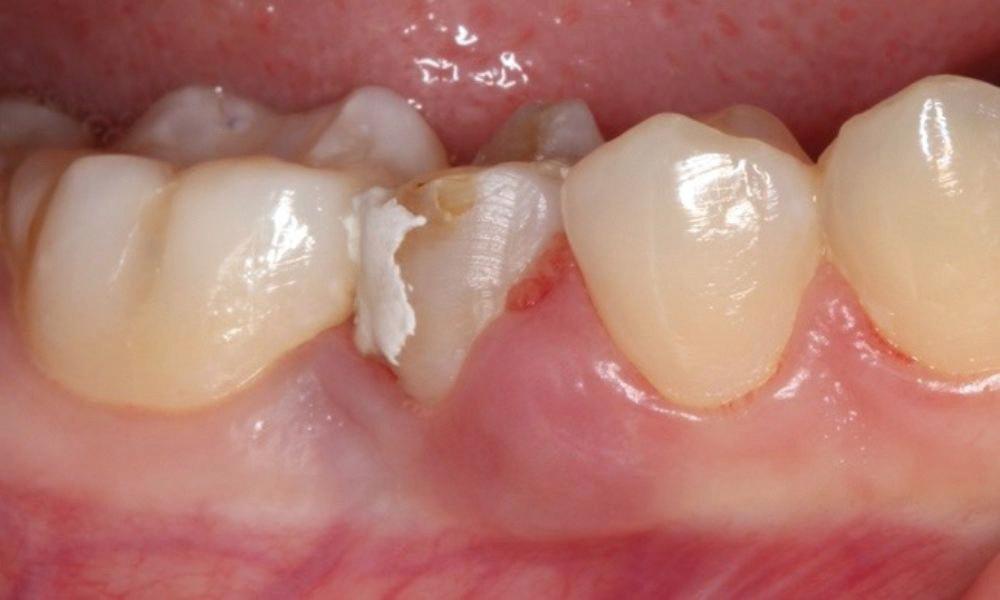

Estelite Asteria (Tokuyama)One of my favourite composite resin materials is Asteria which is a light-cured radiopaque composite for universal use. It considerably simplifies multilayer techniques yet delivers outstanding aesthetics with excellent polishability. Unlike mul tilayer techniques used with conventional composites, Asteria uses only 2 layers for optimal results without compromising aesthetics. The microstructure of the material produces a light diffusion that helps blend in with the natural tooth structure. The chameleon like nature of the material allows a blending of the materials to natural tooth structure and it allows excellent polishability which retains its lustre over time.

“Unlike multilayer techniques used with conventional composites, Asteria uses only 2 layers for optimal results without compromising aesthetics.

The microstructure of the material produces a light diffusion that helps blend in with the natural tooth structure...”